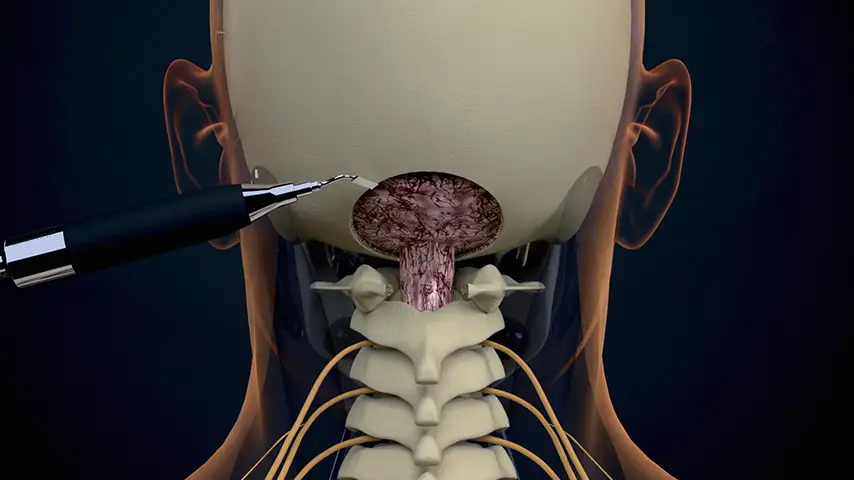

Chiari

malformation

Advantages over traditional tools

Selective cut preserves soft tissue. (Dura, neves and vessels)